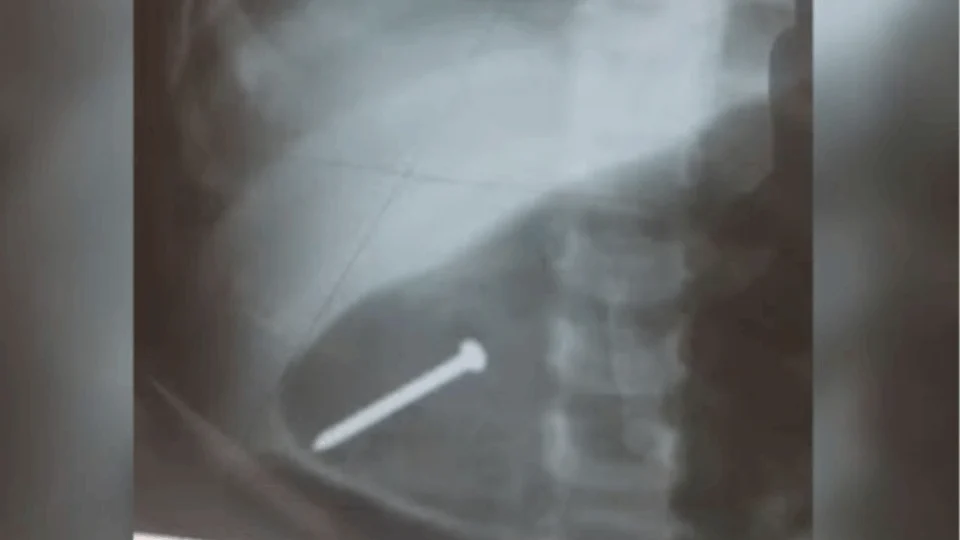

PAÍS | Uma bebê de 1 ano e seis meses acabou precisando ser internada após engolir um prego enquanto brincava dentro de casa. Após um exame de raio-x, os médicos encontraram o objeto dentro do estômago da criança. O caso aconteceu em Breves, no Arquipélago do Marajó, interior do Pará.

De acordo com informações, a menina estava brincando no chão de casa quando encontrou o prego e engoliu. O pai da criança contou que a casa da família está passando por reforma e, apesar do local ter passado por limpeza, o prego acabou ficando. A família desconfiou do problema quando a criança demonstrou que estava engasgada.

Já o hospital, a menina recebeu soro na veia e, segundo os pais, a equipe médica não deixou ela comer ou beber água com receio de que o objeto furasse algum órgão. A Secretaria de Saúde não informou o estado de saúde da criança ou detalhes sobre o procedimento que deve ser realizado.